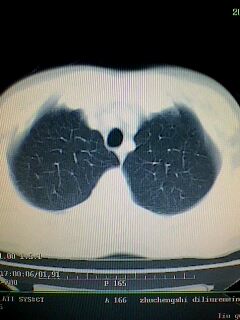

考虑左肺下叶周围型肺癌.图象欠清,请问病人贵更?

考虑左肺下叶周围型肺癌.

图像资料欠清,建议强化,考虑周围型肺癌。

左下肺肿块影,深分叶,考虑肺癌。

左下肺球形病灶,考虑:1:球形肺炎;2:周围型肺癌不除外,建议治疗后复查

不排除左肺下叶周围型肺癌可能!建议穿刺活检!

考虑左肺下叶周围型肺癌。

考虑左肺下叶周围型肺癌并阻塞性肺炎。

考虑左肺下叶周围型肺癌